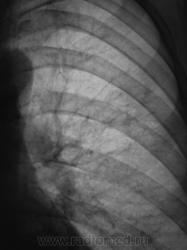

Томограммы.

По мне, так пневмония. Пролечить, посмотреть динамику.

Был нетак давно похожий случай, так же постродал S3,  в связи с локолизацией и консультацией заведующей отправил больного КТД (крайтубдиспансер), там пролечили антибиотиками и отправили домой,  на контроле всё чисто.

Добрый вечер, Валентин Львович. Жалоб нет, или не предъявляет. При туберкулезе - и инфильтрация, и распад, и т.д., а они не предъявляют - тогда ТБС.

Так может быть, без предварительного противовоспалительного лечения - сразу к фтизиатрам?

Да учитывая объём, клинику (отсутствие таковой), можно и сразу к фтизиатрам, но они, мне кажется, полечат сначала антибиотиками.